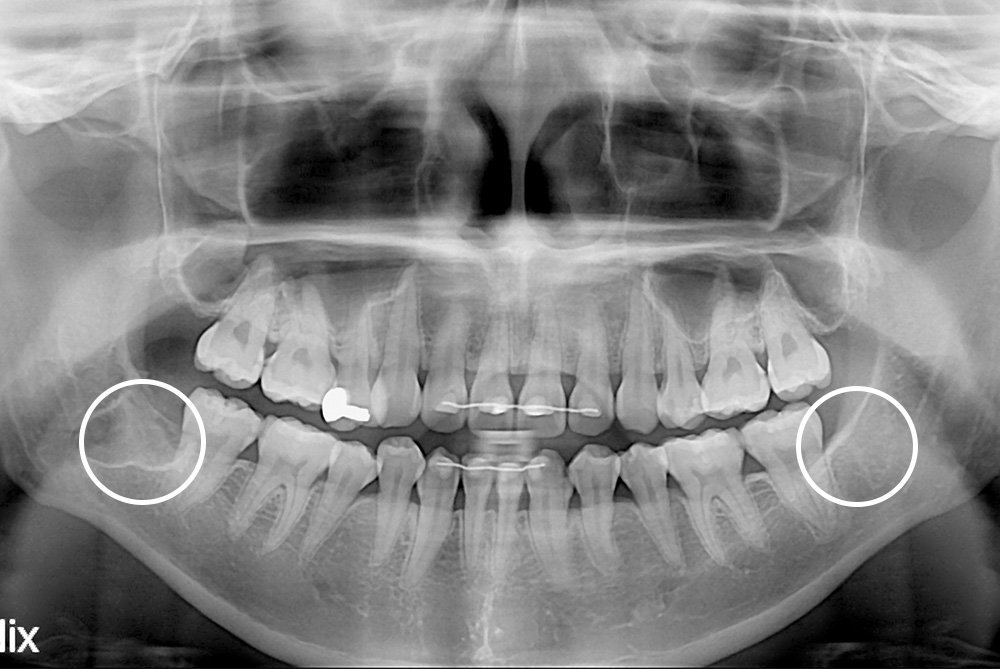

치료후 : 2019-03-28

세종치과는 구강악안면외과학 박사이신 원장님이 발치하는 치과입니다.